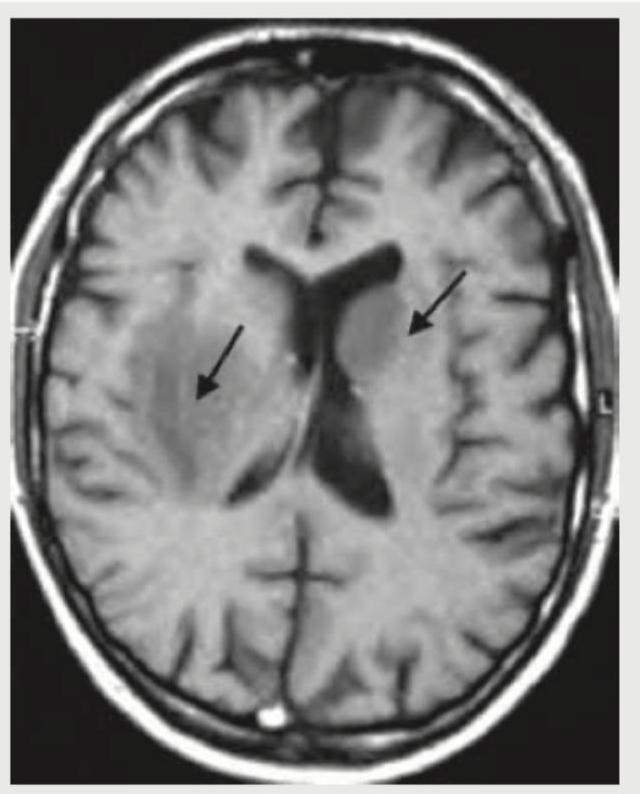

A 6 month infant was brought with complaints of a failure to gain weight and a large head. On examination, increased head circumference, bounding pulses and features of heart failure were noted. On cranial auscultation loud cranial bruit was heard. MRI head shows? (Recent NEET Pattern 2018-19)

Explanation: ***Vein of Galen formation*** - The clinical presentation of **failure to thrive**, **macrocephaly**, **bounding pulses**, **heart failure**, and a **loud cranial bruit** in an infant is highly characteristic of a **Vein of Galen malformation (VOGM)**. The image would show a dilated vein of Galen. - VOGMs are high-flow arteriovenous malformations that can lead to significant hemodynamic stress on the heart and hydrocephalus due to obstruction of CSF pathways. *Arachnoid cyst* - While arachnoid cysts can cause **macrocephaly** and, less commonly, obstructive hydrocephalus, they generally do not present with **heart failure**, **bounding pulses**, or a **cranial bruit**. - MRI would show a CSF-filled cyst that follows CSF signal on all sequences and typically does not enhance. *Arnold-Chiari malformation* - Arnold-Chiari malformations involve downward displacement of cerebellar tonsils or vermis through the foramen magnum and are associated with hydrocephalus, but they do not typically cause **heart failure**, **bounding pulses**, or a **cranial bruit**. - Clinical features usually relate to brain stem compression or hydrocephalus, such as apnea, stridor, or feeding difficulties. *Dandy-Walker syndrome* - Dandy-Walker syndrome is characterized by hypoplasia of the cerebellar vermis and cystic dilation of the fourth ventricle, often leading to **hydrocephalus** and **macrocephaly**. - However, it does not explain the **bounding pulses**, **heart failure**, or **cranial bruit** seen in this patient, which point to a vascular anomaly.